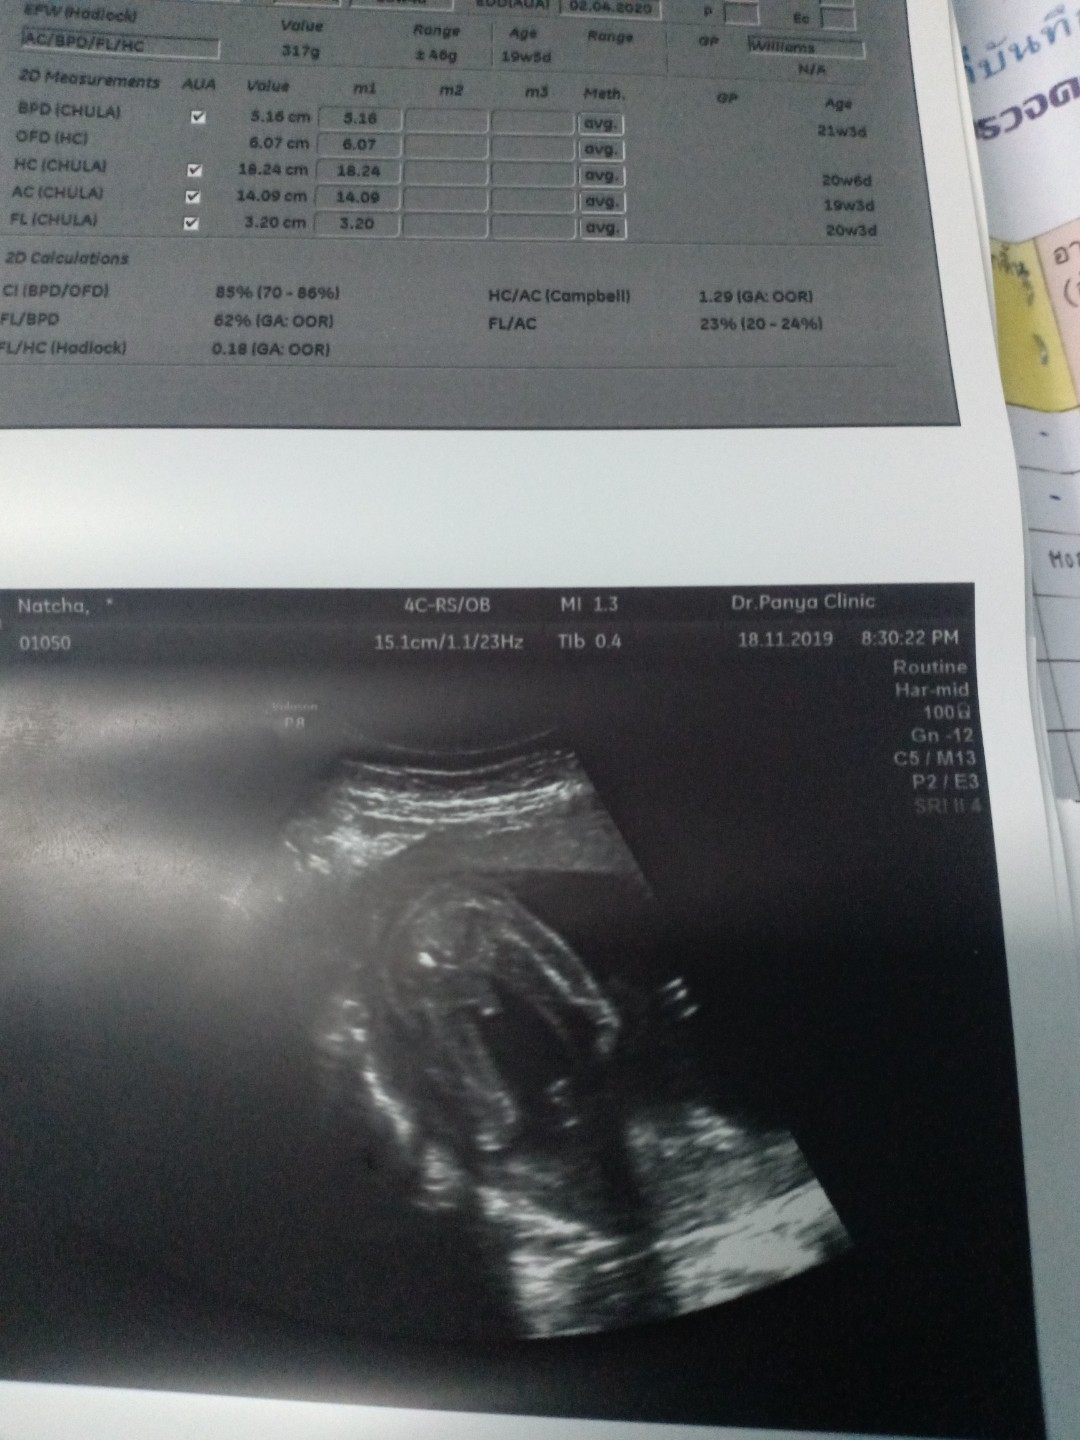

พึ่งซาวด์วันนี้ค่ะ อยากได้ผช. ได้สมใจ ?❤️?